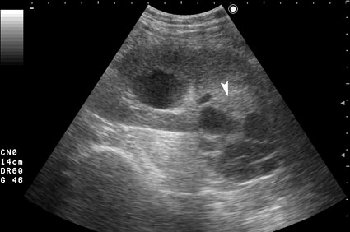

- Серошкальное УЗИ. В области нижнего полюса определяется образование сложной структуры (стрелка).